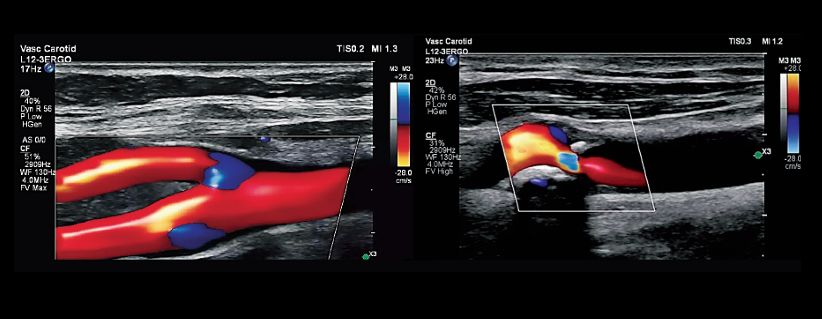

Vascular imaging

Flow Viewer enhances visualization of vascular anatomy by improving depth perception and reducing artifacts.

Two Color Doppler vascular carotid images illustrate the 3D-like visualization and excellent color containment with the vessel lumen offered by Flow Viewer.

As shown above, the technology provides excellent color containment within vessel lumens, helping clinicians assess flow with greater precision.